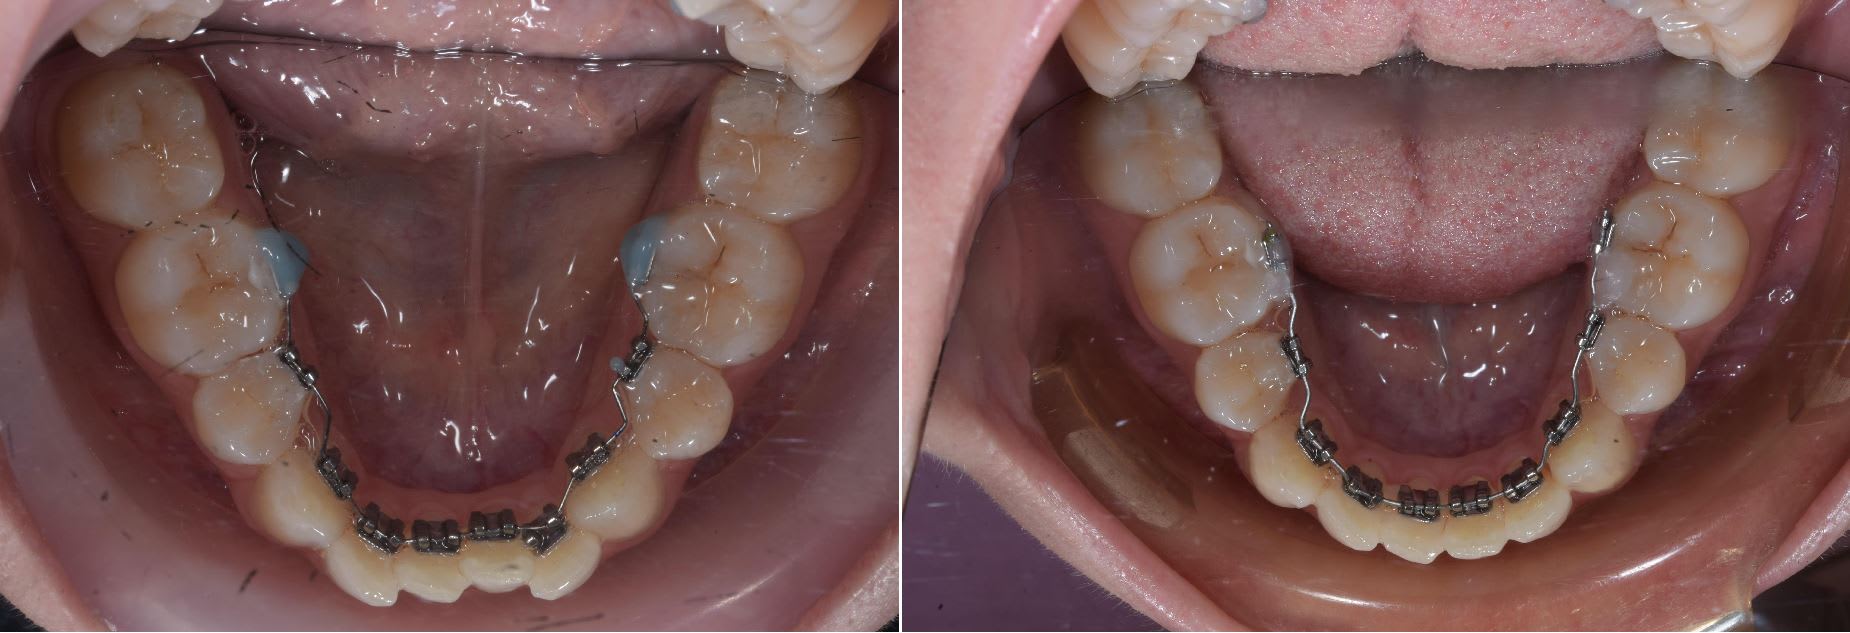

Un petit cas qui montre bien le coté pratique des 2D au niveau de la mise en oeuvre comparé à un appareillage 3D.

Patient qui n'arrivait pas à parler correctement après près de 4 mois avec des 3D. Lui ça ne le dérangé pas trop mais mois si .

Mécaniquement le haut je pense pouvoir traiter avec des 2D sans soucis.

Bref les 2D permettent une flexibilité et réactivité qui est unique parmis les techniques en lingual et ça a très bas cout.